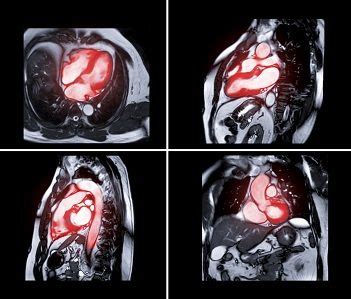

Los adultos que nacieron con bajo peso tenían una respuesta atípica en la obesidad. En una persona con crecimiento fetal adecuado, cuando tiene obesidad, su corazón debe trabajar más y bombear más sangre. Pero en las personas que nacieron con bajo peso, no existe la capacidad de aumentar ni la masa ni el tamaño cardíaco, con lo que su corazón funciona peor, y también empeora la capacidad de hacer ejercicio. La resonancia cardíaca demostró que las personas que habían nacido con bajo peso mantenían cambios en la estructura del corazón en la edad adulta. Su ventrículo derecho tenía una forma diferente.

"Es un estudio pionero, que combina técnicas de análisis computerizada muy sofisticadas para analizar la forma del corazón con resonancia magnética con una prueba de esfuerzo", explica Marta Sitges, directora del Instituto Clínic Cardiovascular, responsable del grupo de investigación del IDIBAPS Imagen cardíaca y coautora del estudio.

Se localizaron personas de entre 20 y 40 años que hubieran nacido con bajo peso y con peso normal. Para ello, se revisaron los libros de la sala de partos del Hospital de Sant Joan de Déu de hace 20-40 años. A partir de la fecha de nacimiento y del apellido de la madre, se logró contactar con algunos de ellos, a los que se les propuso participar en el estudio. Participaron 158 adultos, 81 habían nacido con bajo peso y 77 con peso normal. Se les hizo una resonancia cardíaca y una prueba de esfuerzo en bicicleta.